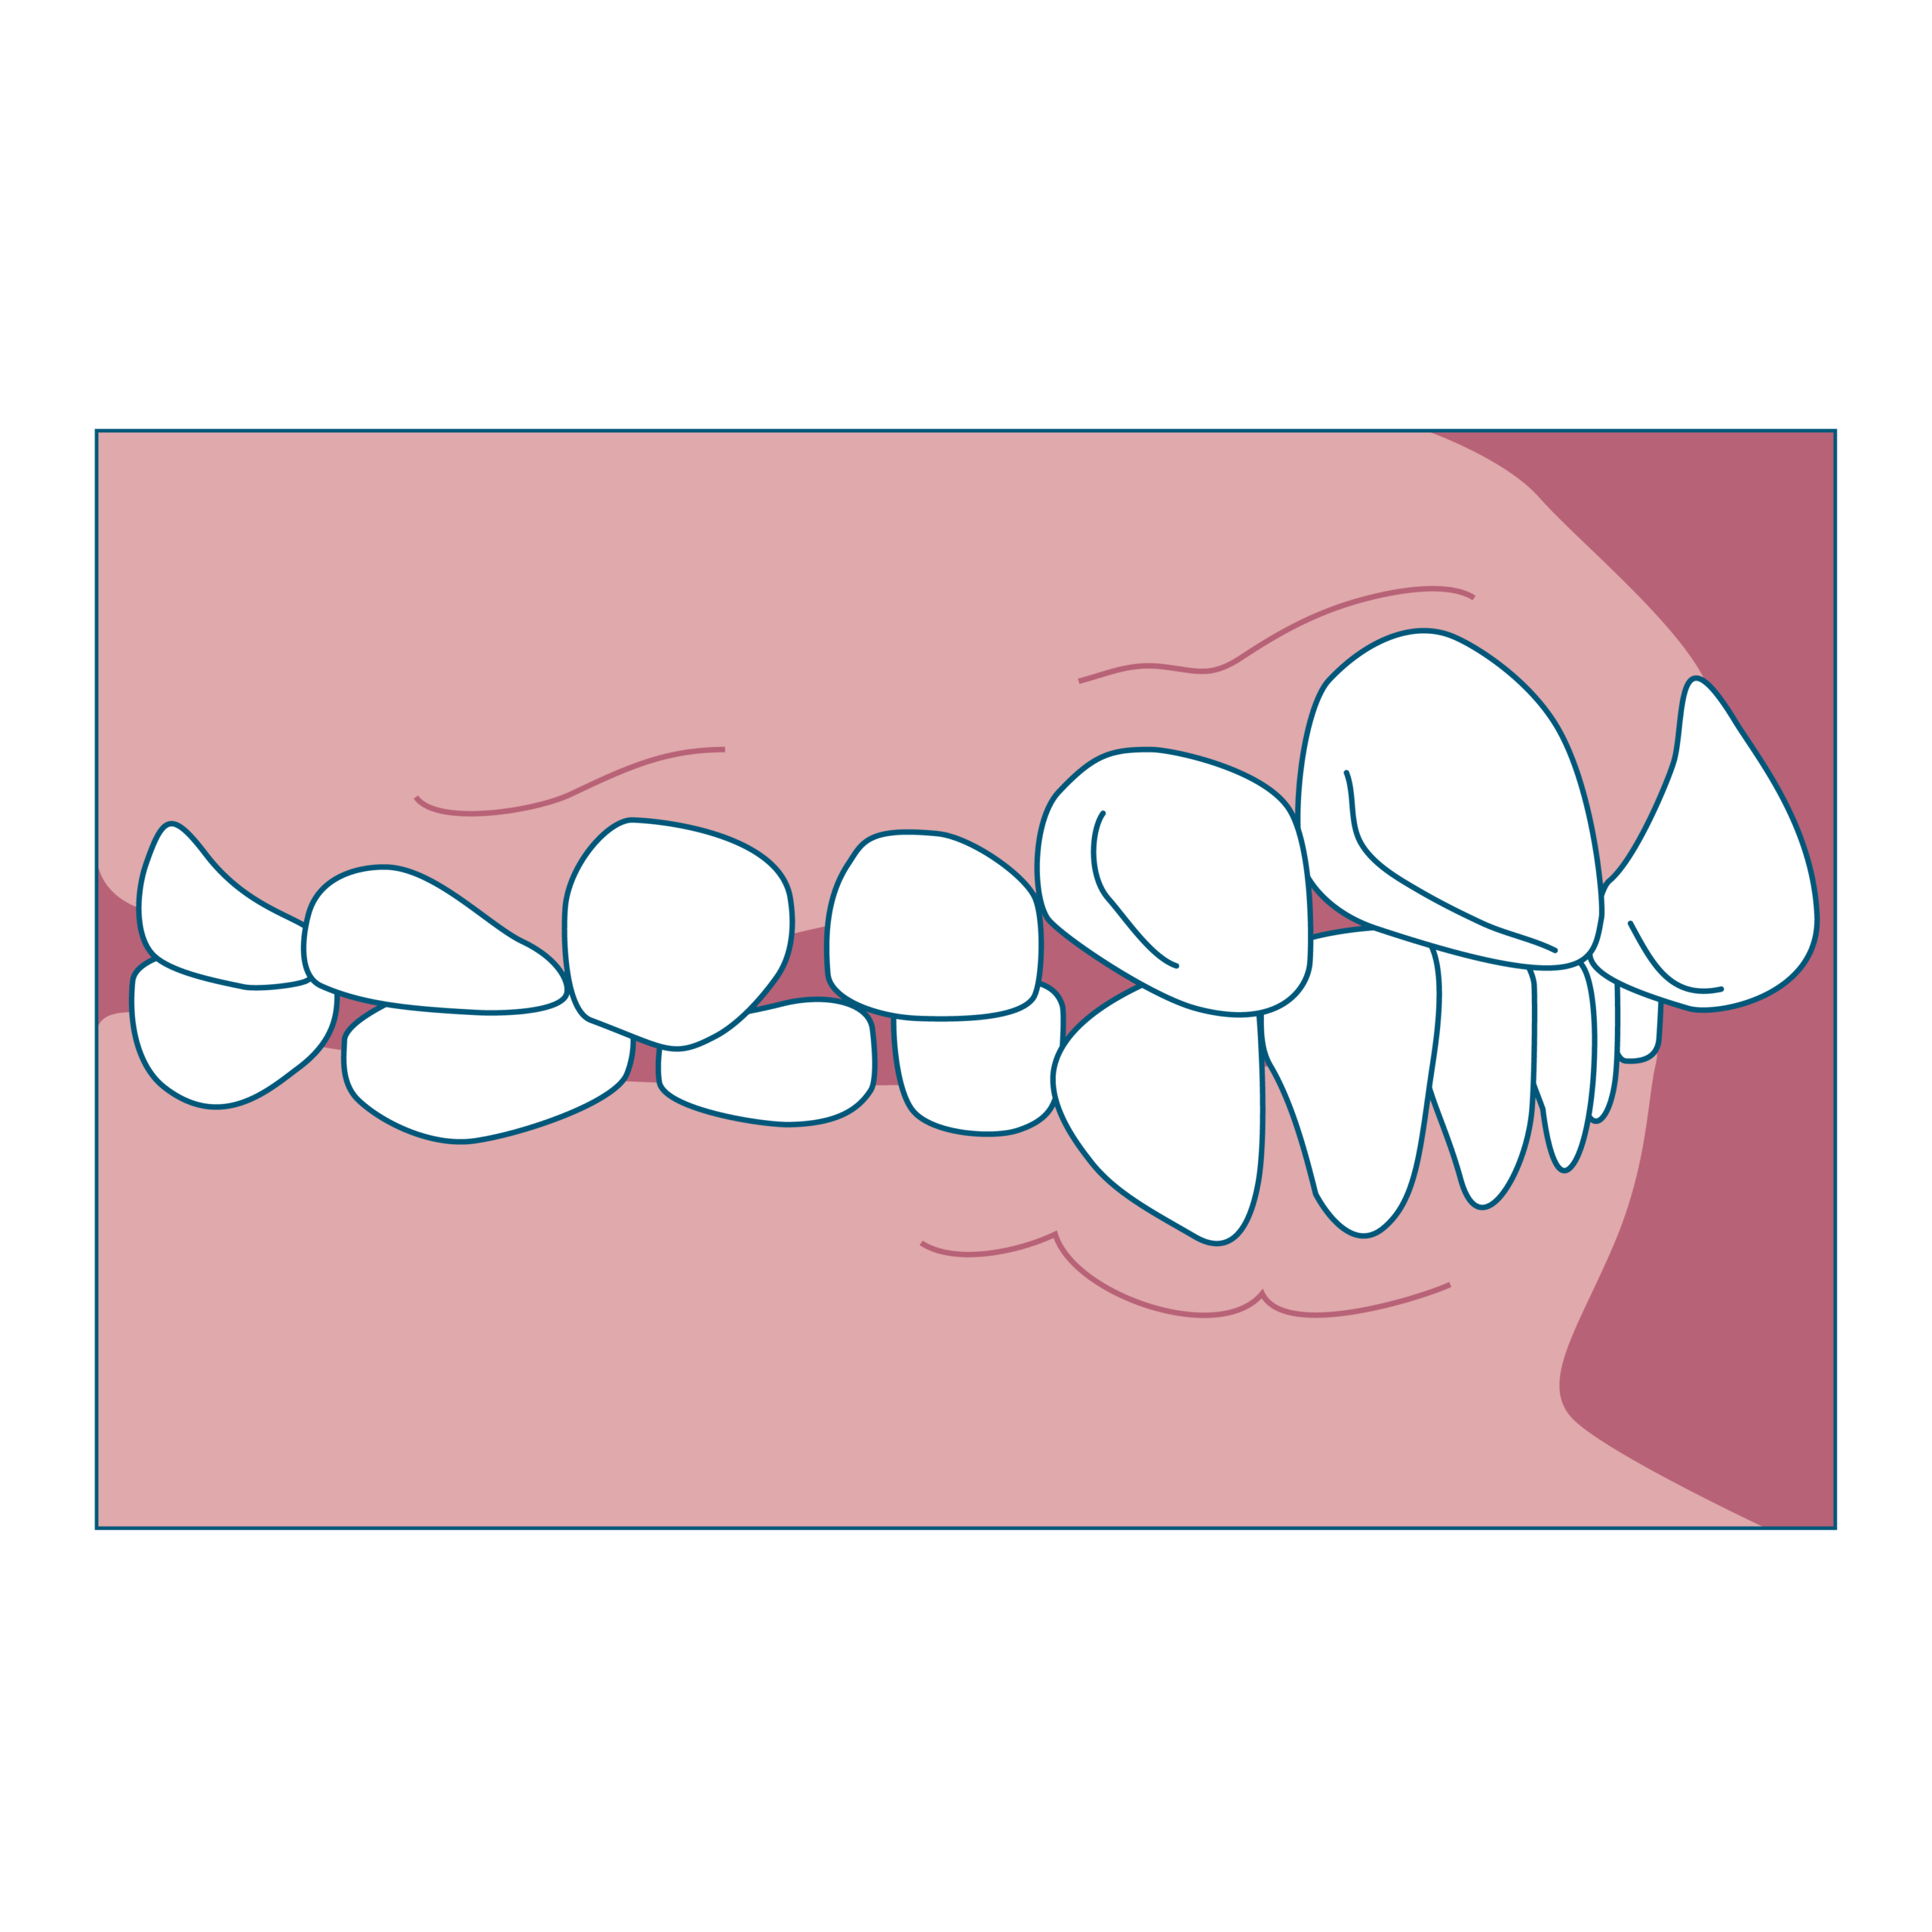

① 出っ歯(上の前歯が前に出ている)

特徴

- 上の前歯が前に突き出している

- 横から見ると口元が出て見える

- 指しゃぶりや口呼吸の癖があるお子さんに多い

始め時

8~10歳ごろ(上の前歯4本、下の前歯4本が永久歯に生え変わったタイミング)がチェックの目安です。出っ歯になってしまっている原因にもよって変わってきますが、骨格的な問題があり、上あごに比べて下あごの成長が乏しかった場合は、上記の年齢がの下あごの成長を促すのに望ましい時期とされています。

ワンポイント

指しゃぶりや口呼吸などの癖をはやめにやめられるよう、生活習慣の改善とセットで進めると効果的です。